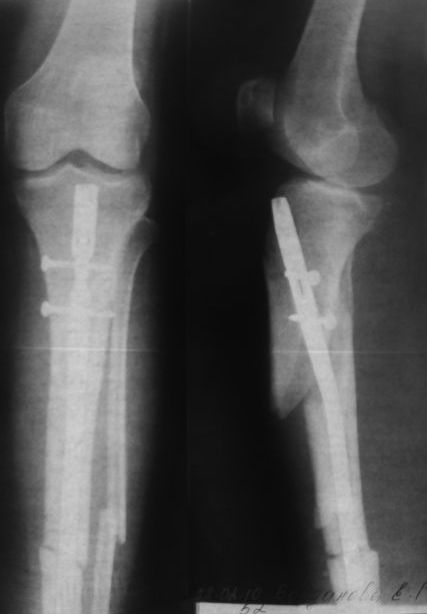

Был тройной перелом голени. Операция была сделана крайне неудачно. Край кости выпирает. Хирург ,проводивший операцию предлагает просто его отпилить. На консультации в другой клинике предлагают извлечь штифт и поставить аппарат Елизарова. Страшно.Подскажите пожалуйста возможно ли исправить ситуацию заменив штифт и правильно соединив обломки. Снимки прилагаю.

Возможно я плохо изложила свою проблему.У меня был перелом обеих костей голени со смещением. 13 января был установлен штифт.Операция была не совсем удачная т.к.сильно выступает острый обломок б.берцовой кости. Очень некрасиво и есть опасность разрыва кожи.

Три ортопеда к которым я обращалась за консультацией считают, что такой результат неприемлем. необходимо извлечь штифт и установить аппарат Илизарова.

Посмотрите снимок.Можно ли оставить всё в таком виде и впоследствии подкорректировать?